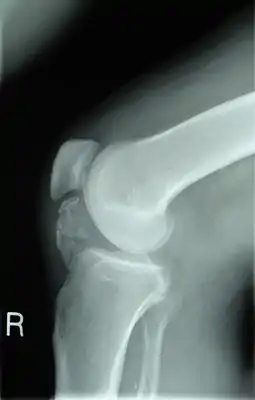

![]() Рентгенограмма колена пациента, больного остеохондромой. Видно окостенение околосухожильных тканей | |